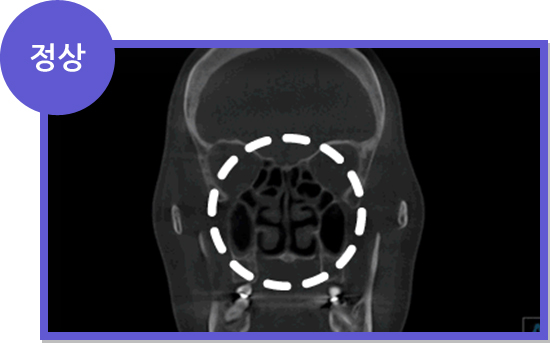

비염 CT 정상 소견 비염 CT 비정상 소견